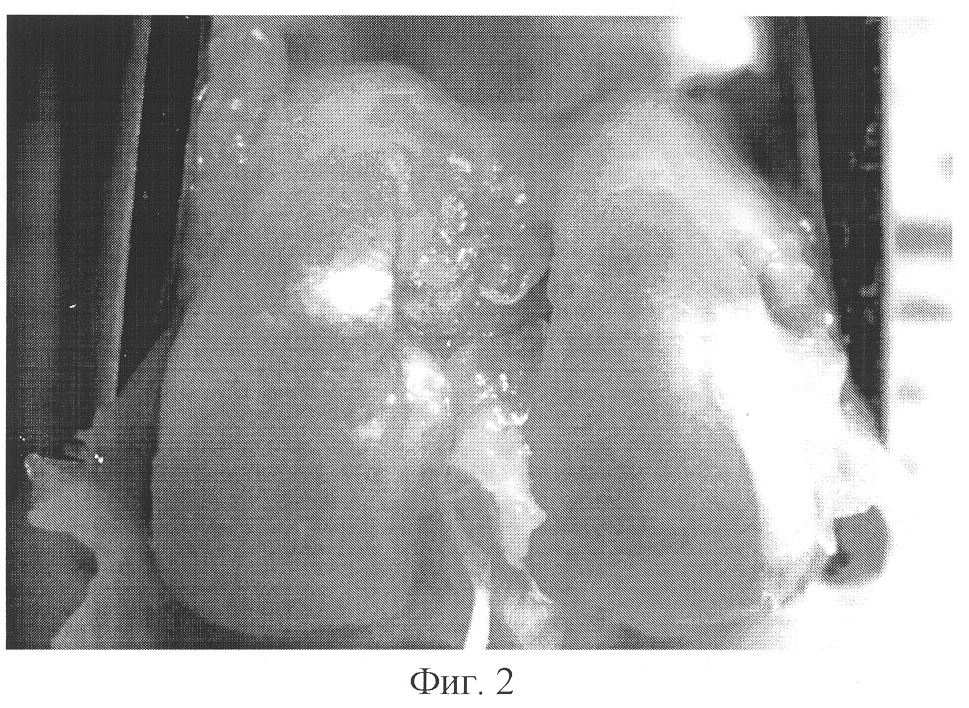

фиг.2 – суставной хрящ мыщелков бедренной кости животного опытной группы через 28 суток после травмы, макропрепарат, ув. Х10;

Макроскопически было установлено, что у всех животных контрольной серии через 28 суток после нанесения травмы суставной хрящ в области мыщелков бедренной кости вне зоны дефекта был шероховатый, матового оттенка (Фиг.1). В опытной серии экспериментов после введения миелопида суставной хрящ в тех же участках был гладкий, прозрачный (Фиг.2).